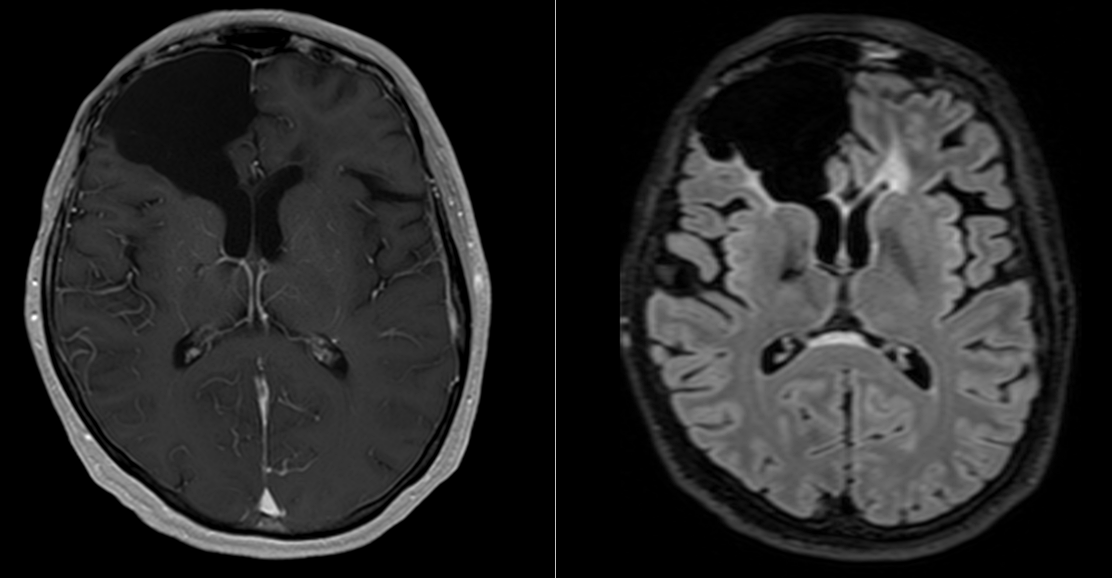

Etapa 3 – Controlul RMN (cu contrast)

- Primul RMN postoperator – la 24 ore de la operație.

- Al doilea RMN – la 3 săptămâni de la operație (va fi folosit și pentru planul de radioterapie).

- Al treilea RMN – la 6 săptămâni de la încheierea radioterapiei.

- Următoarele RMN – la interval de 2 luni.